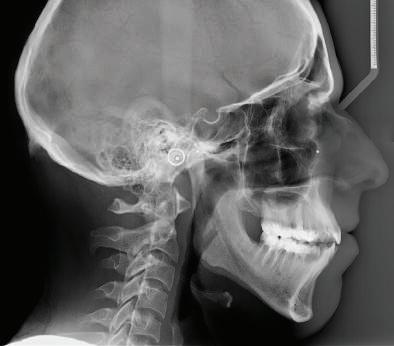

Пациентът постъпи в моята клини ка с наличие на темпоромандибуларен дисфункционален болков синдром, едно странно изместен диск с редукция в дяс ната става, клас II, подклас 2, тесни гор на и долна челюст със струпване, дъл бок овърбайт

орални снимки и снимки на позата, пал пация на мускулите, брукс-чекър, оклу зограми, кондилография, рентгеногра фии, СВСТ и ядрено-магнитен резонанс на темпоромандибуларните стави). Преди началото на ортодонтското лечение всички стари възстановява ния бяха свалени и бяха заменени с дъл госрочни временни от хибридна керами ка. На девитализираните зъби бе прове дено ендодонтско релечение. Индивиду ализиран оклузален сплинт бе направен с цел да се постигне контролирано репо зициониране на долната челюст, като носенето му продължи три месеца до възстановяване на правилната позиция на ставния диск и затихване на орофаци алната болка и дискомфорт в ставата. Брекетите в горната челюст бяха за лепени, за да започне подреждането и нивелирането на зъбите, докато паци ентът все още носеше сплинта. След края на терапията със сплинта бе на правена кондилография, за да се потвър ди триизмерната позиция на долната челюст. След залепване на брекетите в долна

и гингивална усмивка. Започнахме лечението с пълна диагно стика (анамнеза, интраорални, екстра

7Dental Tribune Bulgarian Edition / октомври 2022 г. Преди лечението Фиг. 1 Фиг. 4 Фиг. 7 Фиг. 10 Фиг. 13 Фиг. 16 Фиг. 17 Фиг. 18 Фиг. 19 Фиг. 20 Фиг. 11 Фиг. 14 Фиг. 12 Фиг. 15 Фиг. 8 Фиг. 9 Фиг. 5 Фиг. 6 Фиг. 2 Фиг. 3